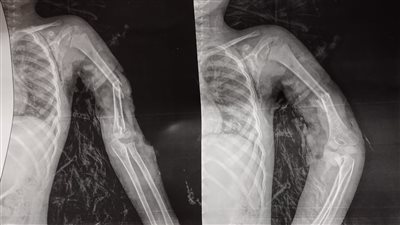

إنقاذ ذراع طفل من بتر كامل بمستشفى سوهاج الجامعي